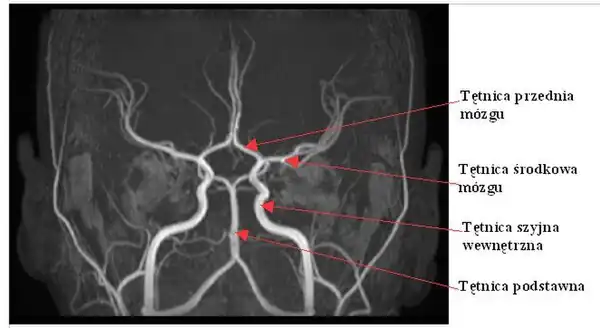

Tętnica środkowa mózgu (łac. arteria cerebri media) – w anatomii człowieka jedna z dwóch końcowych gałęzi tętnicy szyjnej wewnętrznej. Biegnie jako przedłużenie tętnicy szyjnej wewnętrznej, podczas gdy drugie odgałęzienie – czyli tętnica przednia mózgu – odchodzi od tętnicy szyjnej wewnętrznej niemal pod kątem prostym. Niezaliczana do koła tętniczego mózgu[1].

W przebiegu tętnicy środkowej mózgu wyróżnia się trzy części: klinową (M1), wyspową (M2) i korową (M3, M4 i M5). Tętnica środkowa mózgu oddaje dwie grupy odgałęzień: